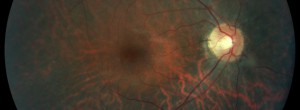

KODIAK: Estudio fase II en pacientes con DMAE forma exudativa.

Ensayo clínico TALON: Eficacia y seguridad de brolacizumab en el tratamiento de la DMAE exudativa

Ensayo clínico LUCERNE: Eficacia y seguridad de FARICIMAB respecto de aflibercept en el tratamiento de la degeneración macular asociada a la edad exudativa